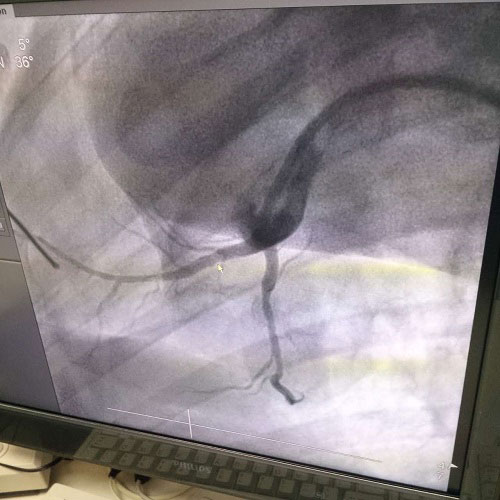

近年來,隨著現代醫療技術的發展和醫療設備的日趨完善,介入性支架治療已經成為介入心血管療法的一種主要手段。血管介入技術是在醫學影像設備的導引下,利用穿刺針、導絲、導管等器械經血管途徑進行診斷與治療的操作技術,已經成為治療各種危險人類健康疾病的最佳方法之一。

目前,臨床上應用的支架種類很多,但是支架的材質多為不銹鋼、鎳-鈦合金或鈷-鉻合金等金屬,這些金屬支架都是生物惰性的,容易引起內膜增生、炎癥反應等。為解決傳統金屬支架的局限性,采用可降解血管支架可以很好地解決傳統金屬支架存在的上述問題。鎂合金因具有適宜的力學性能、組織相容性、低致栓性、低炎性等優點而成為可降解支架的優選材料。

生物全降解鎂合金藥物洗脫支架是我由公司自主立項研發、主要工藝技術完全自主,具有完全自主知識產權。并且可行性強,前期研發基礎扎實,市場需求迫切,實施風險可控,屬全球同行業領先技術,填補國內技術發展空白,符合國家產業發展政策,社會、經濟效益巨大。目前鎂合金藥物支架已進入動物實驗階段,植入動物體內一個月之后效果良好。